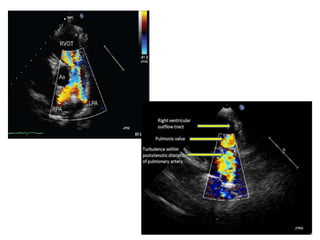

PAs

• The PAs are evaluated using a combination of 2D imaging and

color and spectral Doppler.

• The suprasternal and high left and right parasternal windows

are used to image the mediastinal PAs, although imaging may

be challenging in patients with larger body habitus.

• The main PA (MPA) is measured at its midpoint during systole.

• When supravalvular PA stenosis is present, the smallest

diameter is measured as well. The diameters of the branch

PAs are measured at the level of the origin, and the smallest

dimension of any stenotic segment should be reported.

• The subcostal long-axis, high left parasternal short-axis,

suprasternal short-axis, and right parasternal short-axis

views are helpful in visualizing the length of the RPA.

• The high left parasternal shortaxis and the suprasternal

long-axis (near parasagittal plane angled to the left) views

are useful in visualizing the length of the LPA.

• The distal LPA is more difficult to image than the RPA

because of interference from air in the lung and the left

bronchus.